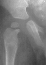

- Hospital Day 6: Respiked to 103.4. R hip Xray showed a defect in proximal

medial metaphysis, Possible osteomyelitis. The child was than taken to

- Post Operative Day 7: Drains removed. Respiked to 101.6. R hip Xray:

suggestion of demineralization of proximal metaphysis. The hip was reaspirated

- Post Operative Day 18: R hip Xray: subluxation of R hip, possible metaphyseal

lucency consistent with osteomyelitis. Taken to OR for repeat I & D